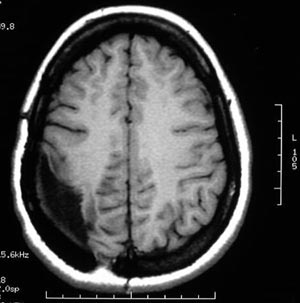

3a) Displasia cortical focal

Figura 55 - Ressonância nuclear magnética pré-operatória.